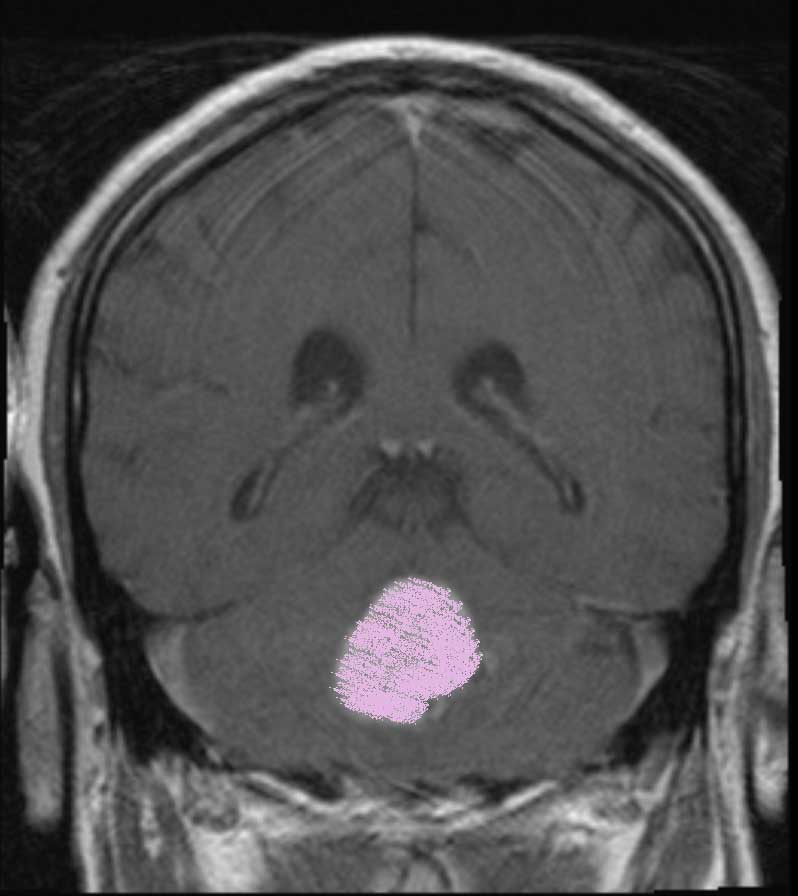

I was diagnosed with a Posterior Fossa tumor 10 days ago.

With that said, the tumor continues to press upon my brain stem and I am in bad shape.

(the lower image shows the Tumor pressing on the brain stem)

(the other white areas are cerebral fluid channels)